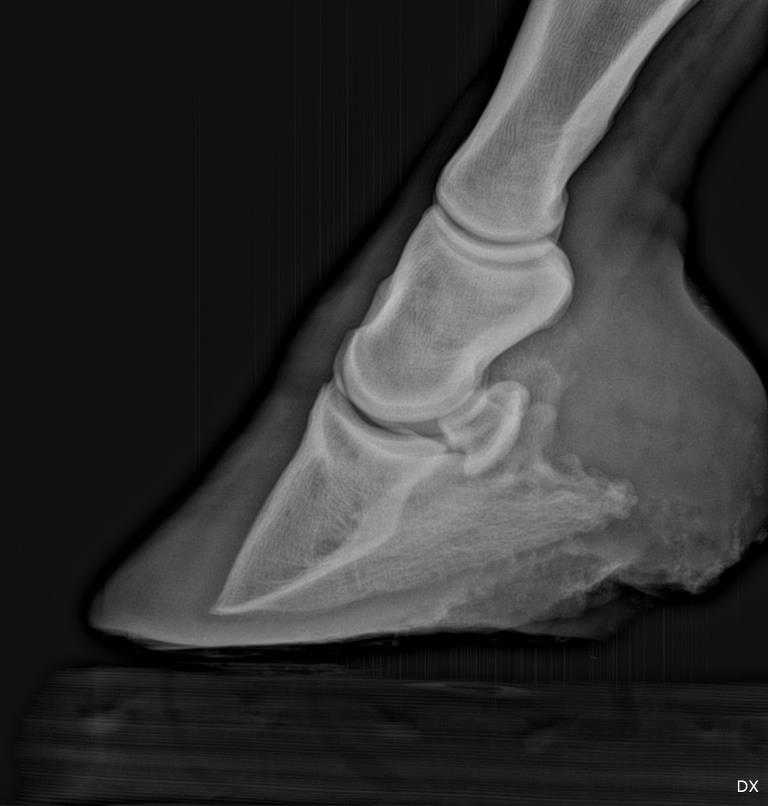

Hi Dr. O, I have posted over the past year and a half about a horse I have with numerous misc problems including rubbing his butt raw. On September 16 he presented very lame in both front feet and with a typical laminitis gait. I had two vets and two farriers look at him. His feet were over grown, the first farrier was due out that week to trim. I have some of this in another post with the original x-rays. Between the four people, it was called thrush, canker, but the x-rays showed rotation. The first farrier trimmed his heels and toes; the vet didn't think it was enough and I had a second farrier trim more to the vets directions. A week later I thought he was worse; vet came out and did more x-rays. He is aligned better but the vet thinks more toe off and has also suggested shoes for heel support. I have read your de-rotation article. This horse is still in pain. I understand each founder is different but I really don't know what direction to go with this horse. I have been keeping him in his stall at night so he can lay down and letting him out in a sand arena during the day. Last week he was having good days and he spent some time in a flat pasture (we have a lot of hills). The vet said his founder was more mechanical from over a period of time of long toes and heels and not to worry about grass. My question is about shoes. The farrier and vet are coming out this Thursday. I am worried about shoes. This horse, has in the past, grown foot fast with lots of toe and heel. I would think I should leave the shoes off until he has less pain and let the hoof wear as it is re-angled. I have thought about using boots on him and not shoes until he has less pain. I will talk with my vet when she comes out but looking for an opinion on boots vs shoes at this point. First picture is left front, second right front.

Left front

One reason your horse remains painful is the trapped sensitive corium between the tip of the coffin bone and the insensitive sole/ground. A shoe will help prevent this pinch but will also remove some support for the coffin bone to prevent further rotation. If the bone is currently stable I would recommend the procedure described in detail in the article associated with this forum. Read it carefully and present the possibility to your vet and farrier to see if they can get on board. If my presumption of the remaining pain is right, it is the quickest way to soundness.